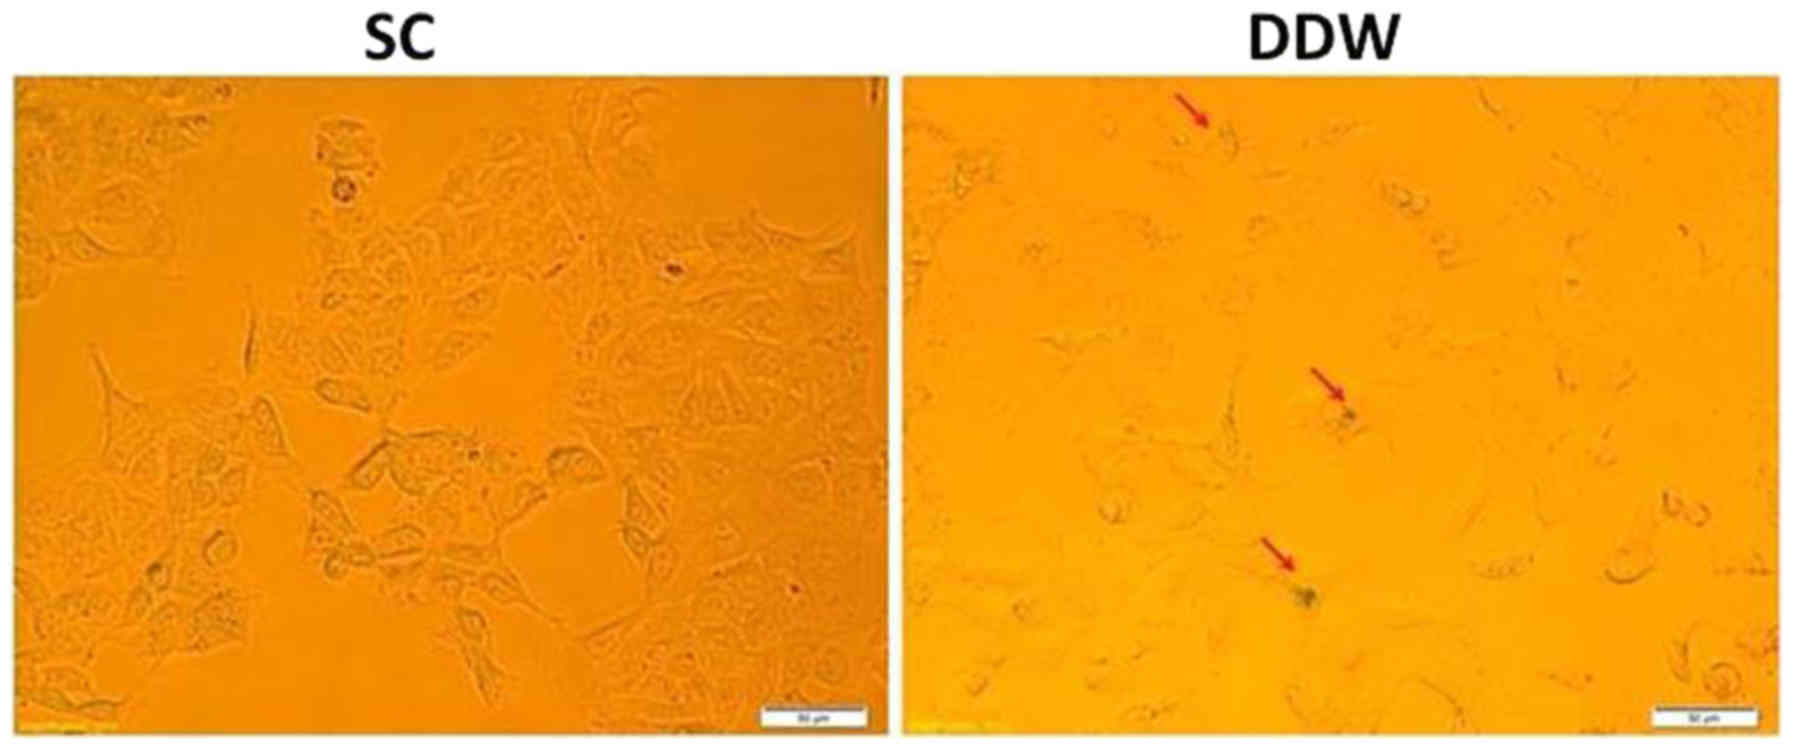

Senescence in the cancer cell line DLD-1 is activated by DDW

It was investigated whether maintaining the cells in DDW was able to induce senescence in the DLD-1 cell line, and therefore offer a novel platform for cancer therapeutics. DLD-1 cells were cultivated for 13 passages in SC or medium prepared with DDW, and were assessed for senescence via detection of β-galactosidase expression. The results indicated a low induction of senescence in cells cultivated in DDW medium compared with those maintained in SC (Fig. 4).

Figure 4.

Evaluation of senescence in DLD-1 colorectal cell line exposed to a low concentration of deuterium. Cells were cultivated for 13 passages in RPMI-1640 medium in SC or low deuterium, and assessed for expression of β-galactosidase (red arrows), which is present in senescent cells only. A slight activation of senescence was observed in cells cultivated in DDW growth medium. DDW, deuterium-depleted water.